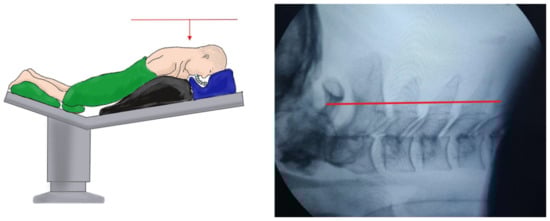

2.3.1. UBE

2.3.2. PE